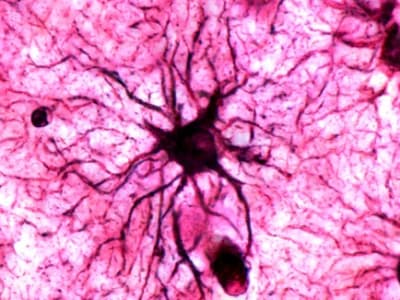

Chip yang digunakan, N1, berukuran sangat kecil dan dilengkapi dengan 128 benang ultra-tipis yang terhubung ke permukaan otak. Benang ini mampu menangkap sinyal saraf dan mengubahnya menjadi perintah digital yang secara presisi menggerakkan perangkat eksternal seperti kursor atau lengan robotik.